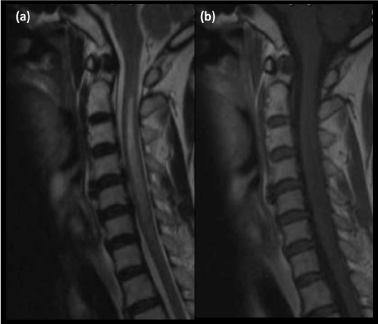

Air embolism can cause infarctions in the posterior circulation. Other potential mechanisms of infarction include arterial perforation causing thrombosis, needle-induced vasospasm, intra-arterial corticosteroid injection and arterial dissection, similar to mechanisms of spinal infarction [4]. Brain infarcts invariably involve the cerebellum, brainstem (Figures 5, 6a and 6b) or posterior cerebral artery territory.  Involvement of the optic radiation and lateral geniculate body would result in hemianopsia while involvement of the thalamic nuclei would cause hemisensory loss. Other possible presenting symptoms include vertigo, ataxia, syncope and dysarthria.

Figure 6. (a)Diffusion-weighted imaging and (b)corresponding ADC map reveal an acute pontine infarct in a patient with sudden onset of weakness post transforaminal steroid injection for symptomatic treatment of cervical spondylosis

MR imaging is excellent in depicting brain infarcts, diffusion-weighted imaging being the most sensitive in the acute settings. Infarcted brain parenchyma would be hyperintense of T2-weighted images and hypointense on T1-weighted images, due to the presence of cytotoxic oedema.